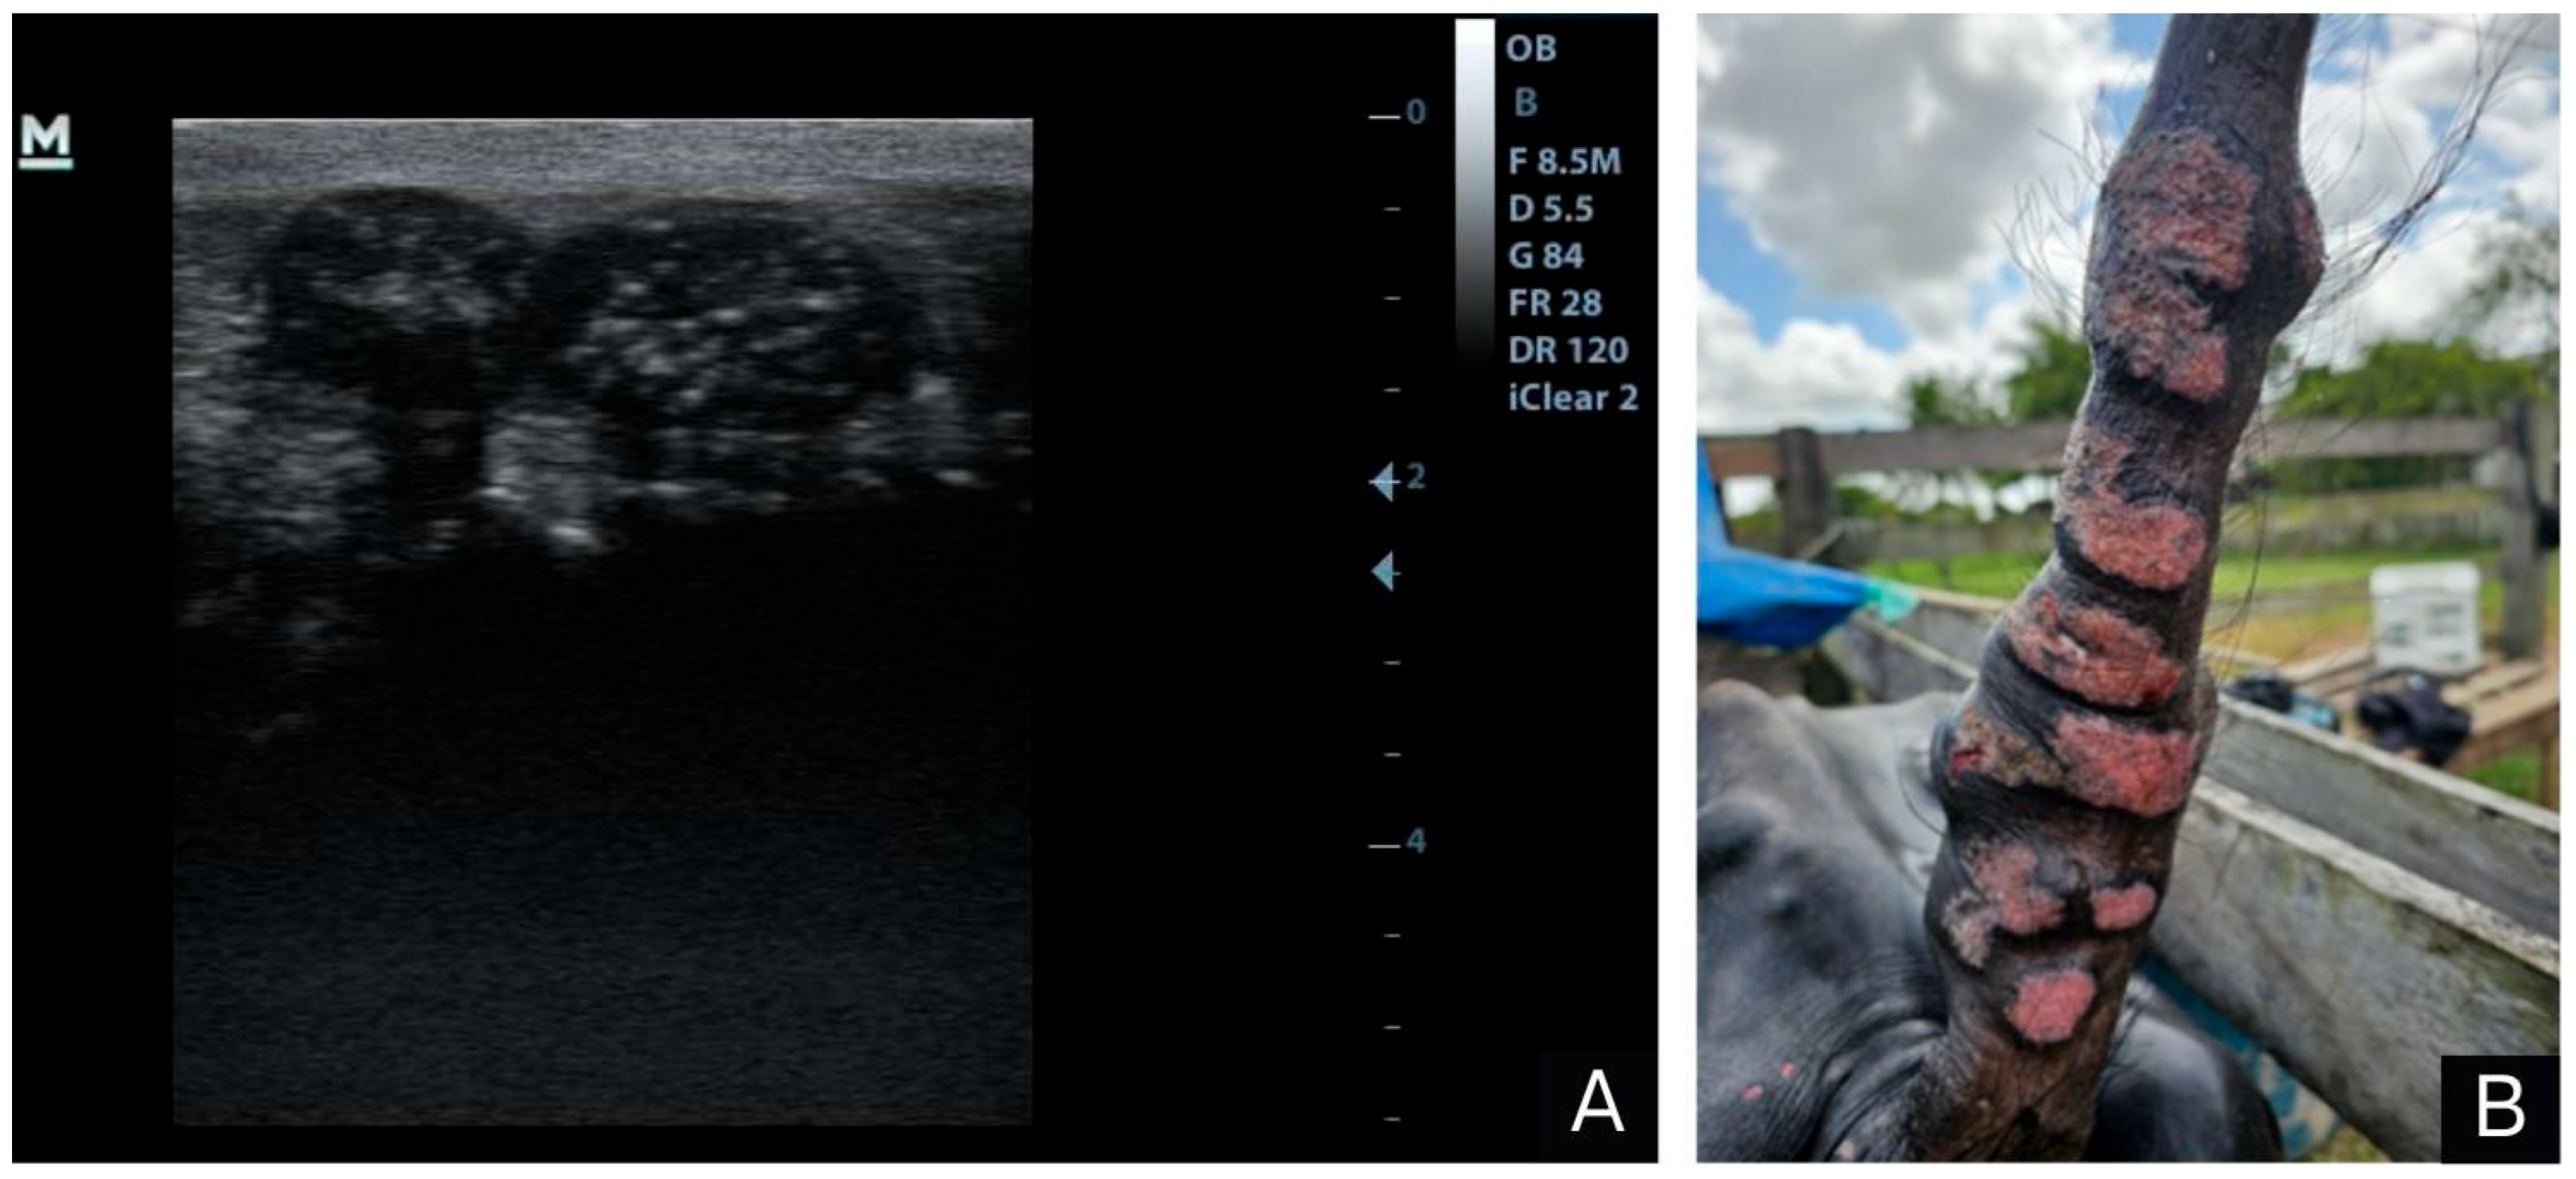

2. Case Report